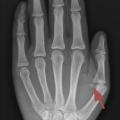

La maturation osseuse est évaluée grâce à une radiographie de la main gauche et du poignet gauche selon la méthode de Greulich et Pyle : c’est l’âge osseux.

Un âge osseux (fig. 4) est réalisé pour confirmer une avance de maturation osseuse. Chez les filles, une échographie pelvienne peut rechercher une imprégnation des organes génitaux internes (augmentation de la hauteur utérine > 35 mm et modification de la morphologie). L’échographie est aussi indiquée pour éliminer une tumeur surrénalienne ou ovarienne, ou des kystes ovariens. En cas de puberté précoce centrale, il convient de réaliser une IRM de la région hypothalamo-hypophysaire. Une imagerie des gonades est en revanche nécessaire dans un contexte de puberté périphérique.